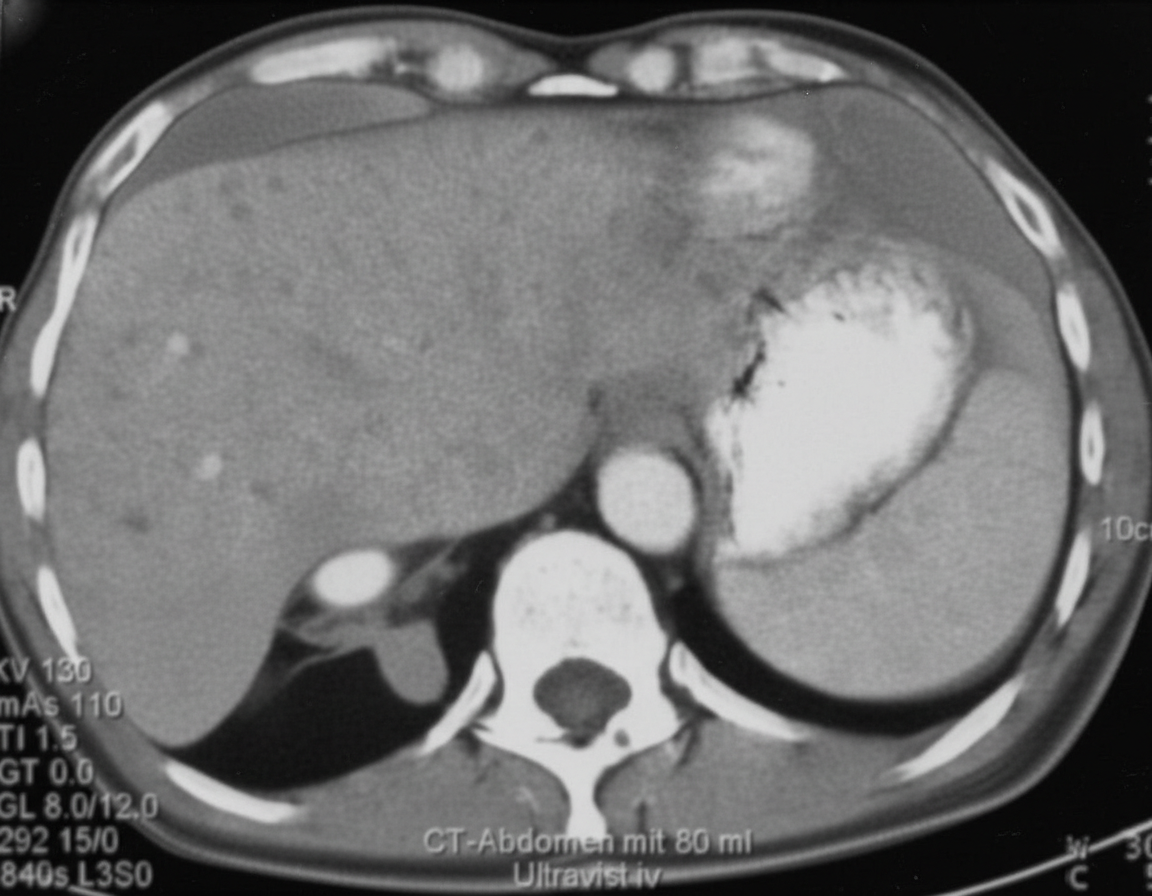

A 64-year-old woman comes to the physician because of a 7.2-kg (16-lb) weight loss over the past 6 months. For the last 4 weeks, she has also had intermittent constipation and bloating. Four months ago, she spent 2 weeks in Mexico with her daughter. She has never smoked. She drinks one glass of wine daily. She appears thin. Her temperature is 38.3°C (101°F), pulse is 80/min, and blood pressure is 136/78 mm Hg. The lungs are clear to auscultation. The abdomen is distended and the liver is palpable 4 cm below the right costal margin with a hard, mildly tender nodule in the left lobe. Test of the stool for occult blood is positive. Serum studies show: Alkaline phosphatase 67 U/L AST 65 U/L ALT 68 U/L Hepatitis B surface antigen negative Hepatitis C antibody negative A contrast-enhanced CT scan of the abdomen is shown. Which of the following is the most likely diagnosis?